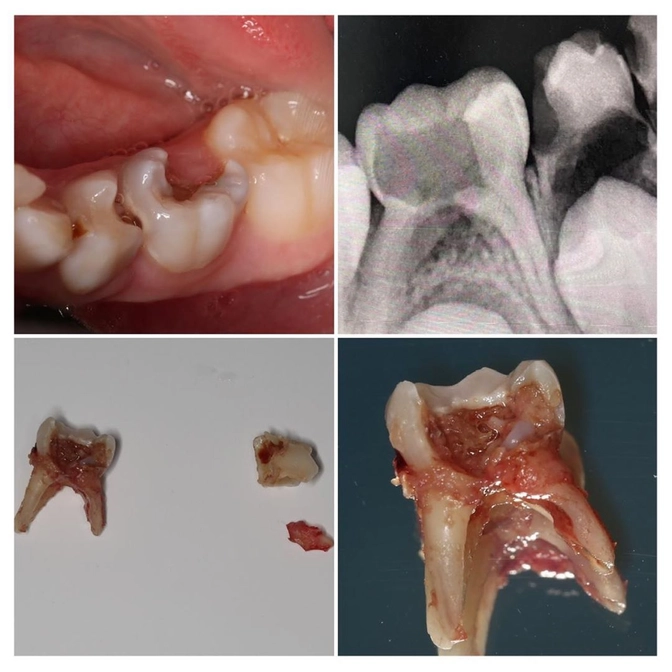

Снимок (он перед вами) тому подтверждение.

Видим, что зуб сильно разрушен.

На снимке четко вырисовывается воспаление, которое уже угрожает зачатку постоянного зуба.

Это "пятерка".

Они меняются примерно в 12 лет.

Ждать и лечить смысла нет.

Зуб удалили.

Всю работу быстро и четко провела детский стоматолог Светлана Кожемякина.

Как видите, "четверка" там тоже поражена кариесом.

Но лечить смысла нет, т.к. она вот-вот поменяется.